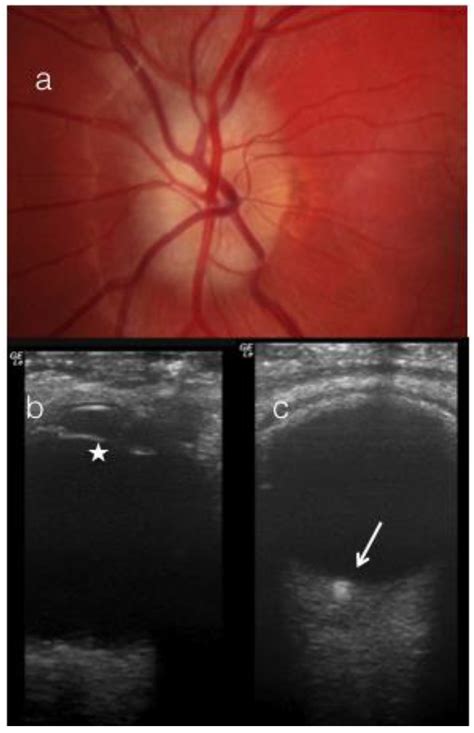

When you undergo a routine eye exam, your optometrist or ophthalmologist uses specialized equipment to peer into the back of your eye, focusing on the optic nerve head. Occasionally, they may notice small, glistening deposits that appear slightly elevated or irregular. These findings are often identified as Optic Nerve Drusen. While the term might sound intimidating, it is crucial to understand that in the vast majority of cases, these are benign, calcified deposits that develop over time within the optic nerve head itself. Although they are generally harmless, their presence can sometimes mimic other, more serious conditions, necessitating a clear understanding of what they are, how they are diagnosed, and when they require clinical attention.

Most individuals with this condition have no idea they have it, as it rarely causes noticeable vision loss in its early stages. However, because the nerve head is crowded by these mineral deposits, the optic disc can appear swollen, which is a condition known as pseudopapilledema. Distinguishing between true papilledema—a dangerous condition involving increased intracranial pressure—and simple, benign drusen is the primary challenge for eye care professionals.

• Disc appearance: During an ophthalmoscopy, the doctor will observe a “bumpy” or “mulberry-like” appearance on the optic nerve head, especially if the drusen are superficial.

Optical Coherence Tomography (OCT): This is the gold standard for non-invasive imaging. It provides high-resolution, cross-sectional images of the optic nerve head, allowing doctors to visualize the calcified deposits directly.

Fundus Autofluorescence (FAF): Because these calcium deposits are naturally fluorescent, FAF imaging can highlight them vividly, making it much easier to distinguish drusen from other tissue structures.